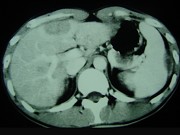

- 单项选择题男,35岁, 病人低热、消瘦、乏力,左右季肋区疼痛, CT扫描如图所示,请选择最佳诊断 ( )

A、肝海绵状血管瘤、腹腔脓肿

B、肝脏及腹腔转移瘤

C、肝脓肿、腹腔脓肿

D、肝癌、腹腔转移

E、肝结核、腹腔结核